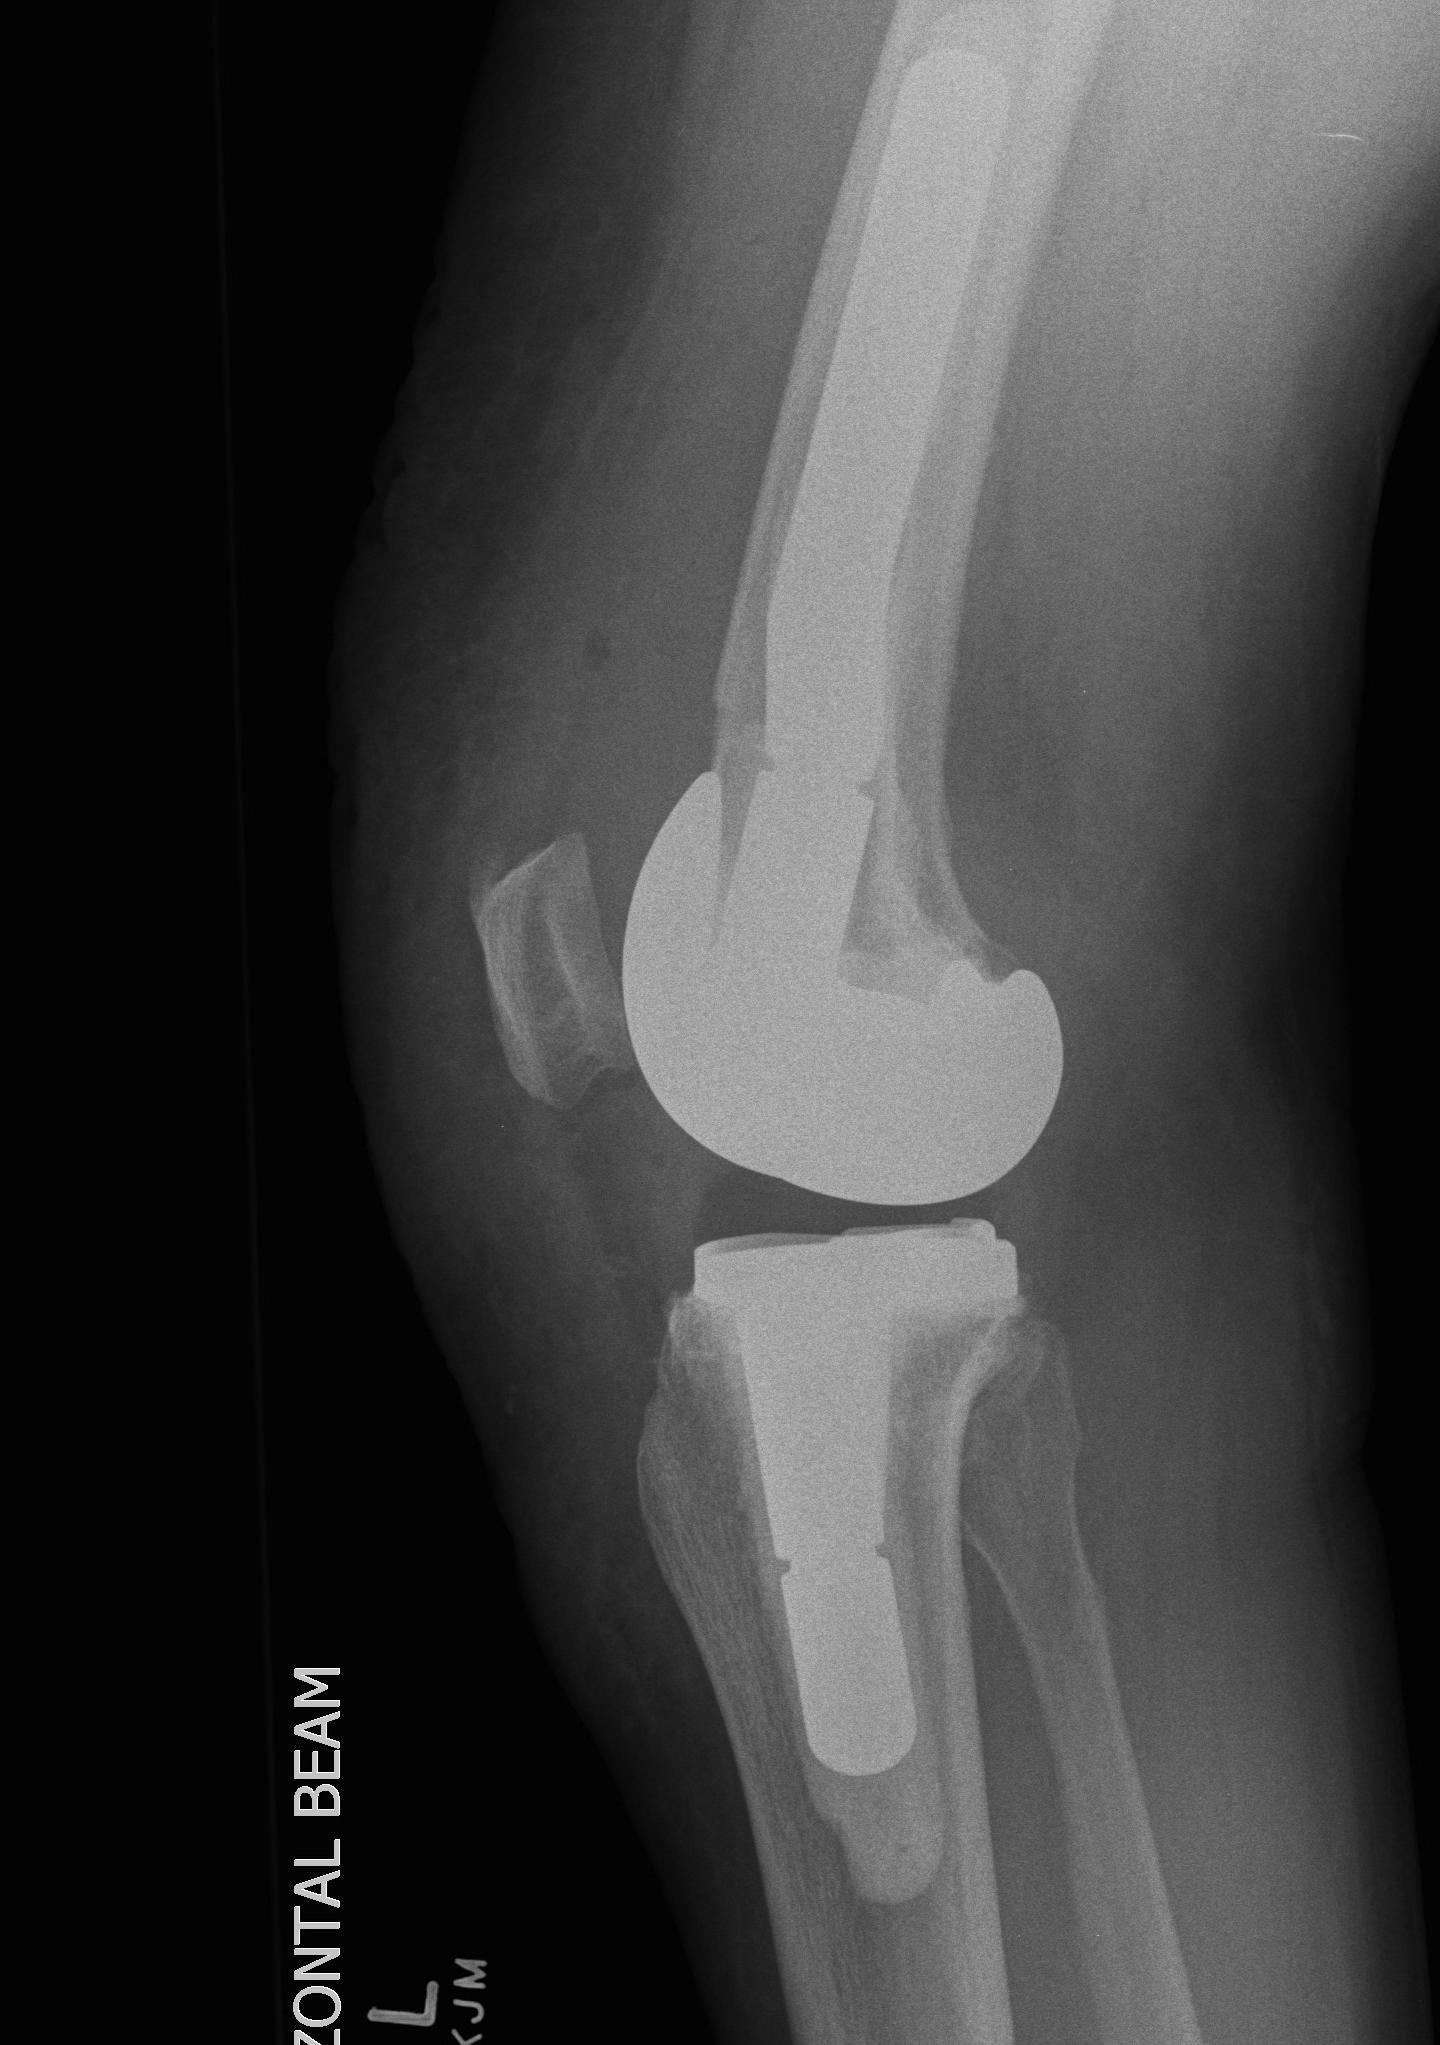

Patient 2